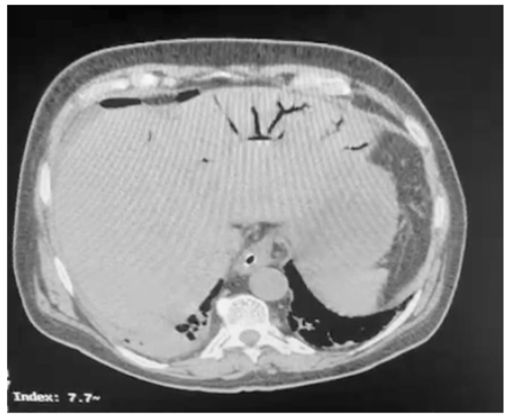

Um paciente de oitenta anos de idade, já com grau de perda de funcionalidade, com períodos de esquecimento, chegou ao pronto-socorro com queda importante do estado geral, com poucas informações objetivas, porém com dor ao exame físico de abdômen. Difícil interpretação dos sinais de irritação peritoneal. Realizou a tomografia abaixo.

Enunciado 3313718-1